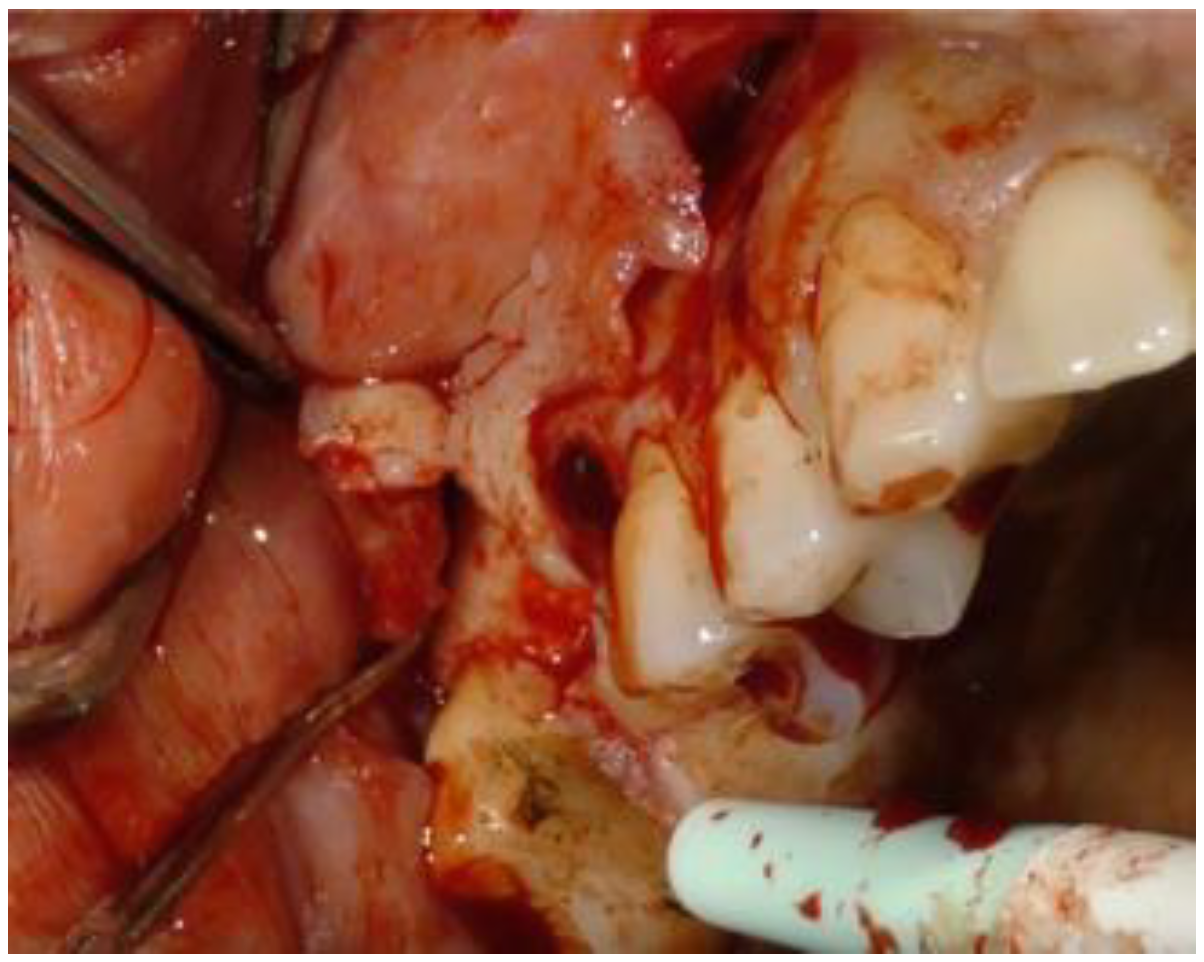

2.1. Clinical and Surgical Procedures